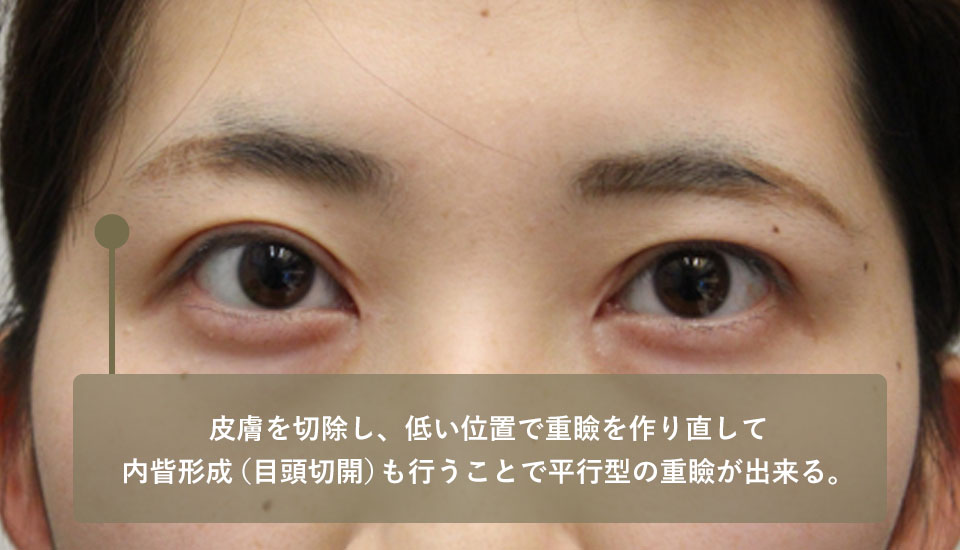

For this reason, this patient underwent an inner corner of the eye incision, upper eyelid skin excision, and heavy eyelid creation. After the surgery, a beautiful parallel heavy eyelid line was created and the patient's expression became natural.

| After surgery | The skin was removed and the lower double eyelid was redraped, and an Eyebrow lift was also performed to create a parallel double eyelid. |

| After surgery | After an Eyebrow lift and a double eyelid makeover, the eye size ratio was about 1:2 lengthwise and widthwise, which is natural. |